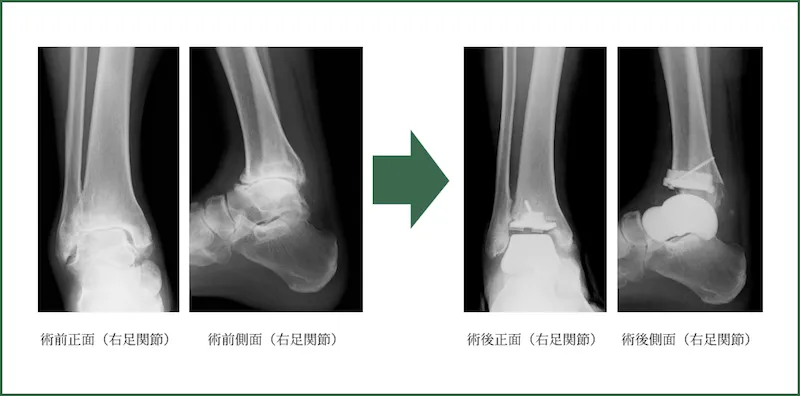

人工足関節置換術

全身シールド装置(サージカルヘルメット)を使用しております。

手術時間:平均120分

出血量:平均30ml

2021年10月より開始致しました。

脛骨側をTNK Ankle、距骨を人工距骨全置換術 (Kyocera)によるTAA combinedで行います。

人工距骨はカスタムメイドです。